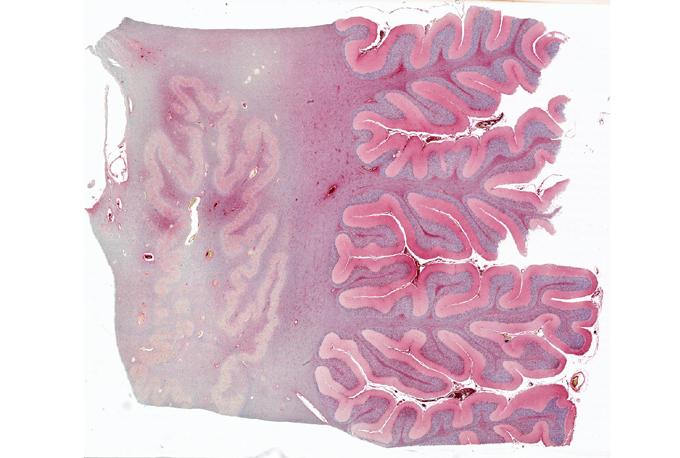

Among the cells that release inflammatory proteins in the brain are microglia, the brain’s version of the body’s disease-fighting immune system. Microglia may also be involved in the brain’s response to COVID-19. Microglia primed for action were found in about 43 percent of 184 COVID-19 patients, Singer and others reported in a review published February 4 in Free Neuropathology. Similar results come from a series of autopsies of COVID-19 patients’ brains; 34 of 41 brains contained activated microglia, researchers from Columbia University Irving Medical Center and New York Presbyterian Hospital reported April 15 in Brain.